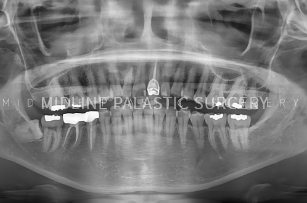

첫째, 3D-CT로 얼굴 뼈 촬영

둘째, CT, X-ray로 얼굴 뼈 전체 분석

셋째, 개개인에 맞는 섬세한 수술 계획

CT 촬영

3D-CT로 촬영한 데이터를 기반으로 얼굴뼈

전체를 정밀하게 분석하여 보다 안전하고

정확한 수술 계획이 가능합니다.